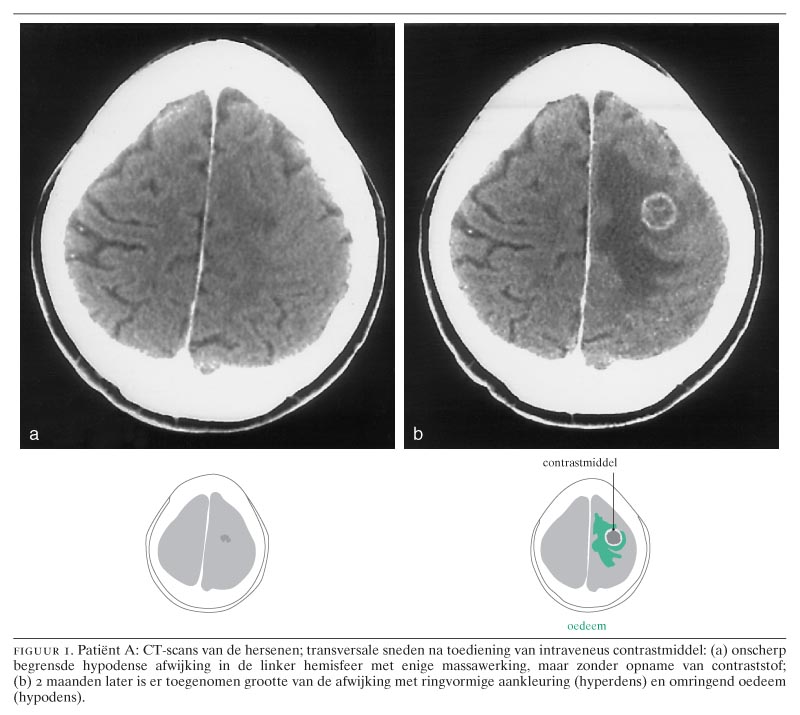

Hersentumor of beroerte? Nederlands Tijdschrift voor Geneeskunde